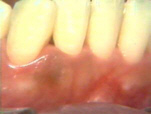

Dos semanas después del

tratamiento la gingiva tiene una apariencia pálida saludable. El paciente ha practicado los procedimientos

eficaces de higiene oral desde el tratamiento. |

Aquí la condición

gingival en lingual es saludable después de un par de semanas del

tratamiento. |

| El lado derecho presenta

la misma condición gingival que el izquierdo. |

Después de 2 meses del

tratamiento la gingiva es saludable y las profundidades de los

surcos (bolsas) periodontales están reducidas. No se observa

sangrado al sondaje. |